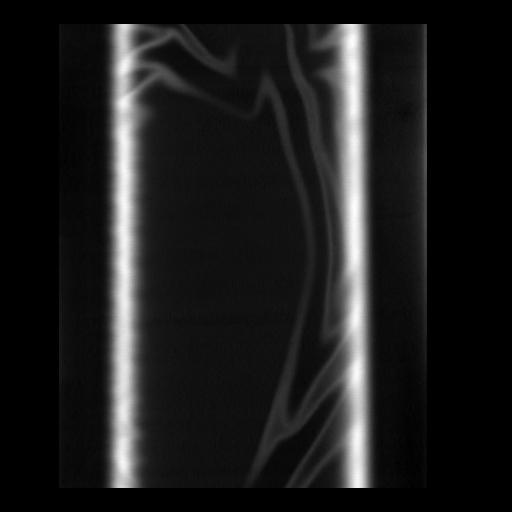

35 CUERPO,CE,Coronal,3.000,CUERPO,Coronal,